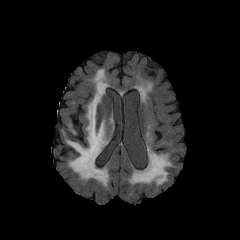

We obtain a subject-wise mean Dice score of 63.67% for the brain tumor segmentation. Utilizing a simple post-processing scheme of erosion and dilation with filter, we improve our mean Dice score to 68.01%. Figure 4 shows samples generated by our ASC-Net and Table 2 shows our before and after post-processing results. We attempted to apply f-AnoGANs [34] by following their online instructions and failed to generate good reconstructions as shown in Figure 5. The failure of AnoGANs in the reconstruction brings to light the issue with the regeneration based methods and the complexity and stability of GAN-based image reconstruction.

A most recent work in [27] trains their algorithm using 1,112 healthy scans from the Human Connectome Project (HCP) young adult dataset [38] and tests on 50 random BraTS 2018 scans, obtaining a mean dice score of 67.2% and 15.5% standard deviation. Following our simple post-processing scheme, our algorithm performs better, increasing the mean Dice score by 0.81% and reducing the standard deviation by 0.97%, on two-fold cross validation across 335 scans. Another work in [42] tests on the BraTS 2018 training set, obtaining a mean dice score of 71.63% and standard deviation of 0.84%. While their method outperforms ours, it is worth to mention that the self-supervised method is highly specialized to a particular task of tumor segmentation. It may happen that the object to be segmented is difficult to synthesize artificially or perfectly, resulting in a bottleneck of the pipeline. Furthermore, one assumption of a self-supervised learning algorithm is that the object to be learnt is known beforehand. Thus, a model trained for brain tumors cannot be applied readily to other anomalies, e.g., brain lesions. Our method, on the other hand, has no such limitations and does not need Pseudo dataset generation for a new task. That is, our method is a general approach for anomaly detection and segmentation. Also, our method performs better than [42] on the liver lesion segmentation task after post-processing.

We obtain a slice-wise mean Dice score of 32.24% for this liver lesion segmentation, which improves to 50.23% by using a simple post processing scheme of erosion and dilation with filter. Sampled results are shown in Fig. 4. Compared with [42], which obtains a mean Dice score of 40.78% and a standard deviation of 0.43%, we improve the mean Dice score by almost 10%, but has a much larger standard deviation. Unlike [42], where the network is pre-trained on a artificial tumor dataset, and hence the pipeline customized for tumor segmentation, our method do not need such information beforehand. We notice that our standard deviation for BraTS dataset is similar to [27]. This is because novelty/anomaly detection algorithms without a pre-defined task would suffer from the co-morbidities issues discussed in Section 5.